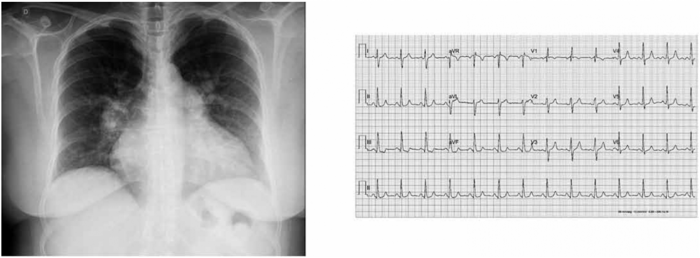

Paciente de 13 anos, masculino, apresenta antecedente de Doença de Kawasaki diagnosticado aos 4 meses de idade, tratado com gamaglobulina 2g/kg com 12 dias de sintomas. O ecocardiograma da época apresentava dilatação de artérias coronárias esquerda e direita. Desde então faz uso de ácido acetilsalicílico e, posteriormente, de atorvastatina. Nos ecocardiogramas posteriores, as artérias coronárias não apresentavam lesões residuais. Há um mês, o paciente passou a referir dores do tipo pontada com duração de segundos no repouso, sem piora aos esforços ou necessidade de medicações para dor ou procurar pronto-socorro. Foram realizados novos exames: radiografia de tórax normal, eletrocardiograma de 12 derivações normal, ecocardiograma normal, teste ergométrico com segmento ST com infradesnivelamento durante o esforço e angiotomografia de coronárias com escore total de cálcio coronariano de 202 (Agatston) e 175 mm3 (Volume), no percentil 99% para a faixa etária e sexo, além de ectasia de tronco de artéria coronária esquerda e artéria circunflexa e artéria coronária direita com redução luminal acentuada. Qual a conduta a ser tomada?